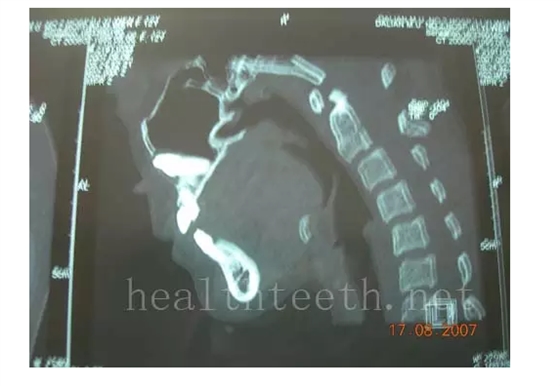

通過CT片確定埋伏牙齒具體的位置,顯示距離左側上頜竇很近,偏唇側,這為手術定位提供了方便

QQ圖片20150722094055.png

QQ圖片20150722094148.png

手術中切斷、完整拔出,未損傷上頜竇